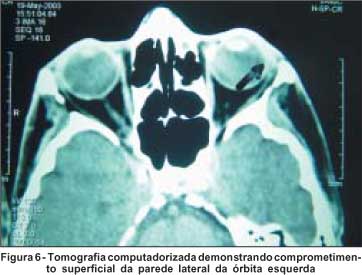

Paciente branca, sexo feminino, 68 anos de idade, com história de trauma em face, principalmente na região periorbitária esquerda há dois anos, sendo atendida em outro serviço. Há um ano notou irritação no canto lateral esquerdo, sem melhora com o uso de medicação tópica (sic). A paciente referia piora do quadro com o passar dos meses, procurando nosso serviço para tratamento (Figura 5). Ao exame foi observado edema na pálpebra superior, apresentando-se com aspecto brilhante, hiperemiada, com perda dos cílios e pequena ulceração com pontos hemorrágicos. A pálpebra inferior estava comprometida na sua metade lateral. Observou-se também, que a paciente apresentava lesão do ramo frontal do nervo facial, provavelmente devido ao trauma de face. Foi solicitada avaliação clínica pré-operatória, bem como tomografia computadorizada das órbitas com cortes coronais e axiais. Esta revelou comprometimento tanto da pálpebra superior quanto da inferior e invasão superficial da parede lateral da órbita esquerda (Figura 6). A paciente foi submetida à ressecção da lesão sob anestesia geral, sendo retirado aproximadamente 90% da pálpebra superior e 65% da pálpebra inferior. Também foi ressecada parcialmente a parede lateral da órbita esquerda (Figura 7). Durante a cirurgia as margens foram examinadas através de biópsia de congelação, orientando o cirurgião quanto ao seu comprometimento ou não. Todo o material foi enviado para exame anatomopatológico, que diagnosticou carcinoma basocelular invasivo, com todas as margens livres. A reconstrução das pálpebras foi realizada através do uso do retalho de Fricke, sendo modificado seu desenho, devido as cicatrizes existentes na face da paciente (Figura 8). Após quatro meses de pós-operatório, esta paciente não apresenta sinal de recidiva (Figura 9).